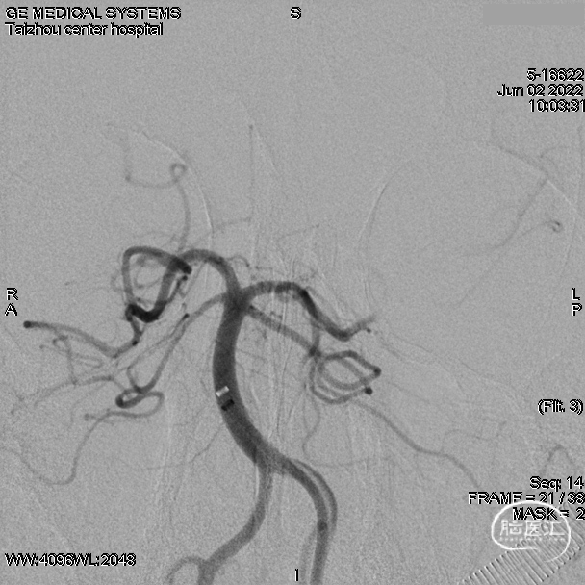

术后即刻头颅CT

术后6h头颅CT

术后3d头颅CT

引流术后头颅CT

出院:意识清楚,查体欠配合,右上肢肌力III级,右下肢肌力II级,双侧巴氏征阴性。房颤心律。

头颅CT